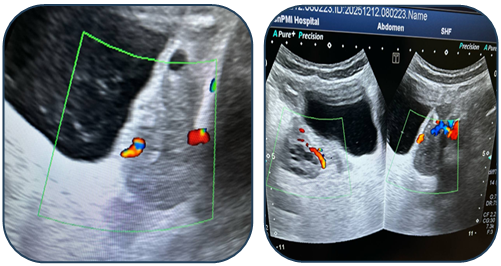

Case 1: A 17-year-old female presented with acute pain. Ultrasound revealed a 95 mm complex left ovarian cyst with no Doppler flow (Fig. 1). Emergency laparoscopy confirmed a 720-degree torsion. Detorsion and cystectomy were performed. Intraoperative findings are shown in Fig. 2, Fig. 3, and Fig. 4. Histopathology reported a serous cystadenoma. Postoperative ultrasound on day 5 confirmed a viable ovary (Fig. 5). | Figure 1. Ultrasound findings of a left ovarian cyst with torsion |

| Figure 2. Intraoperative laparoscopic view 1 |

| Figure 3. Intraoperative laparoscopic view 2 |

| Figure 4. Intraoperative laparoscopic view 3 |